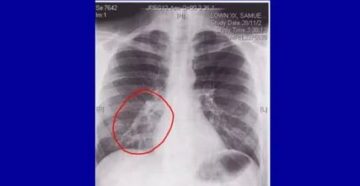

Бронхит на рентгеновском снимке Часто пациенты задают вопрос: «Почему не назначают рентген при бронхите, все…